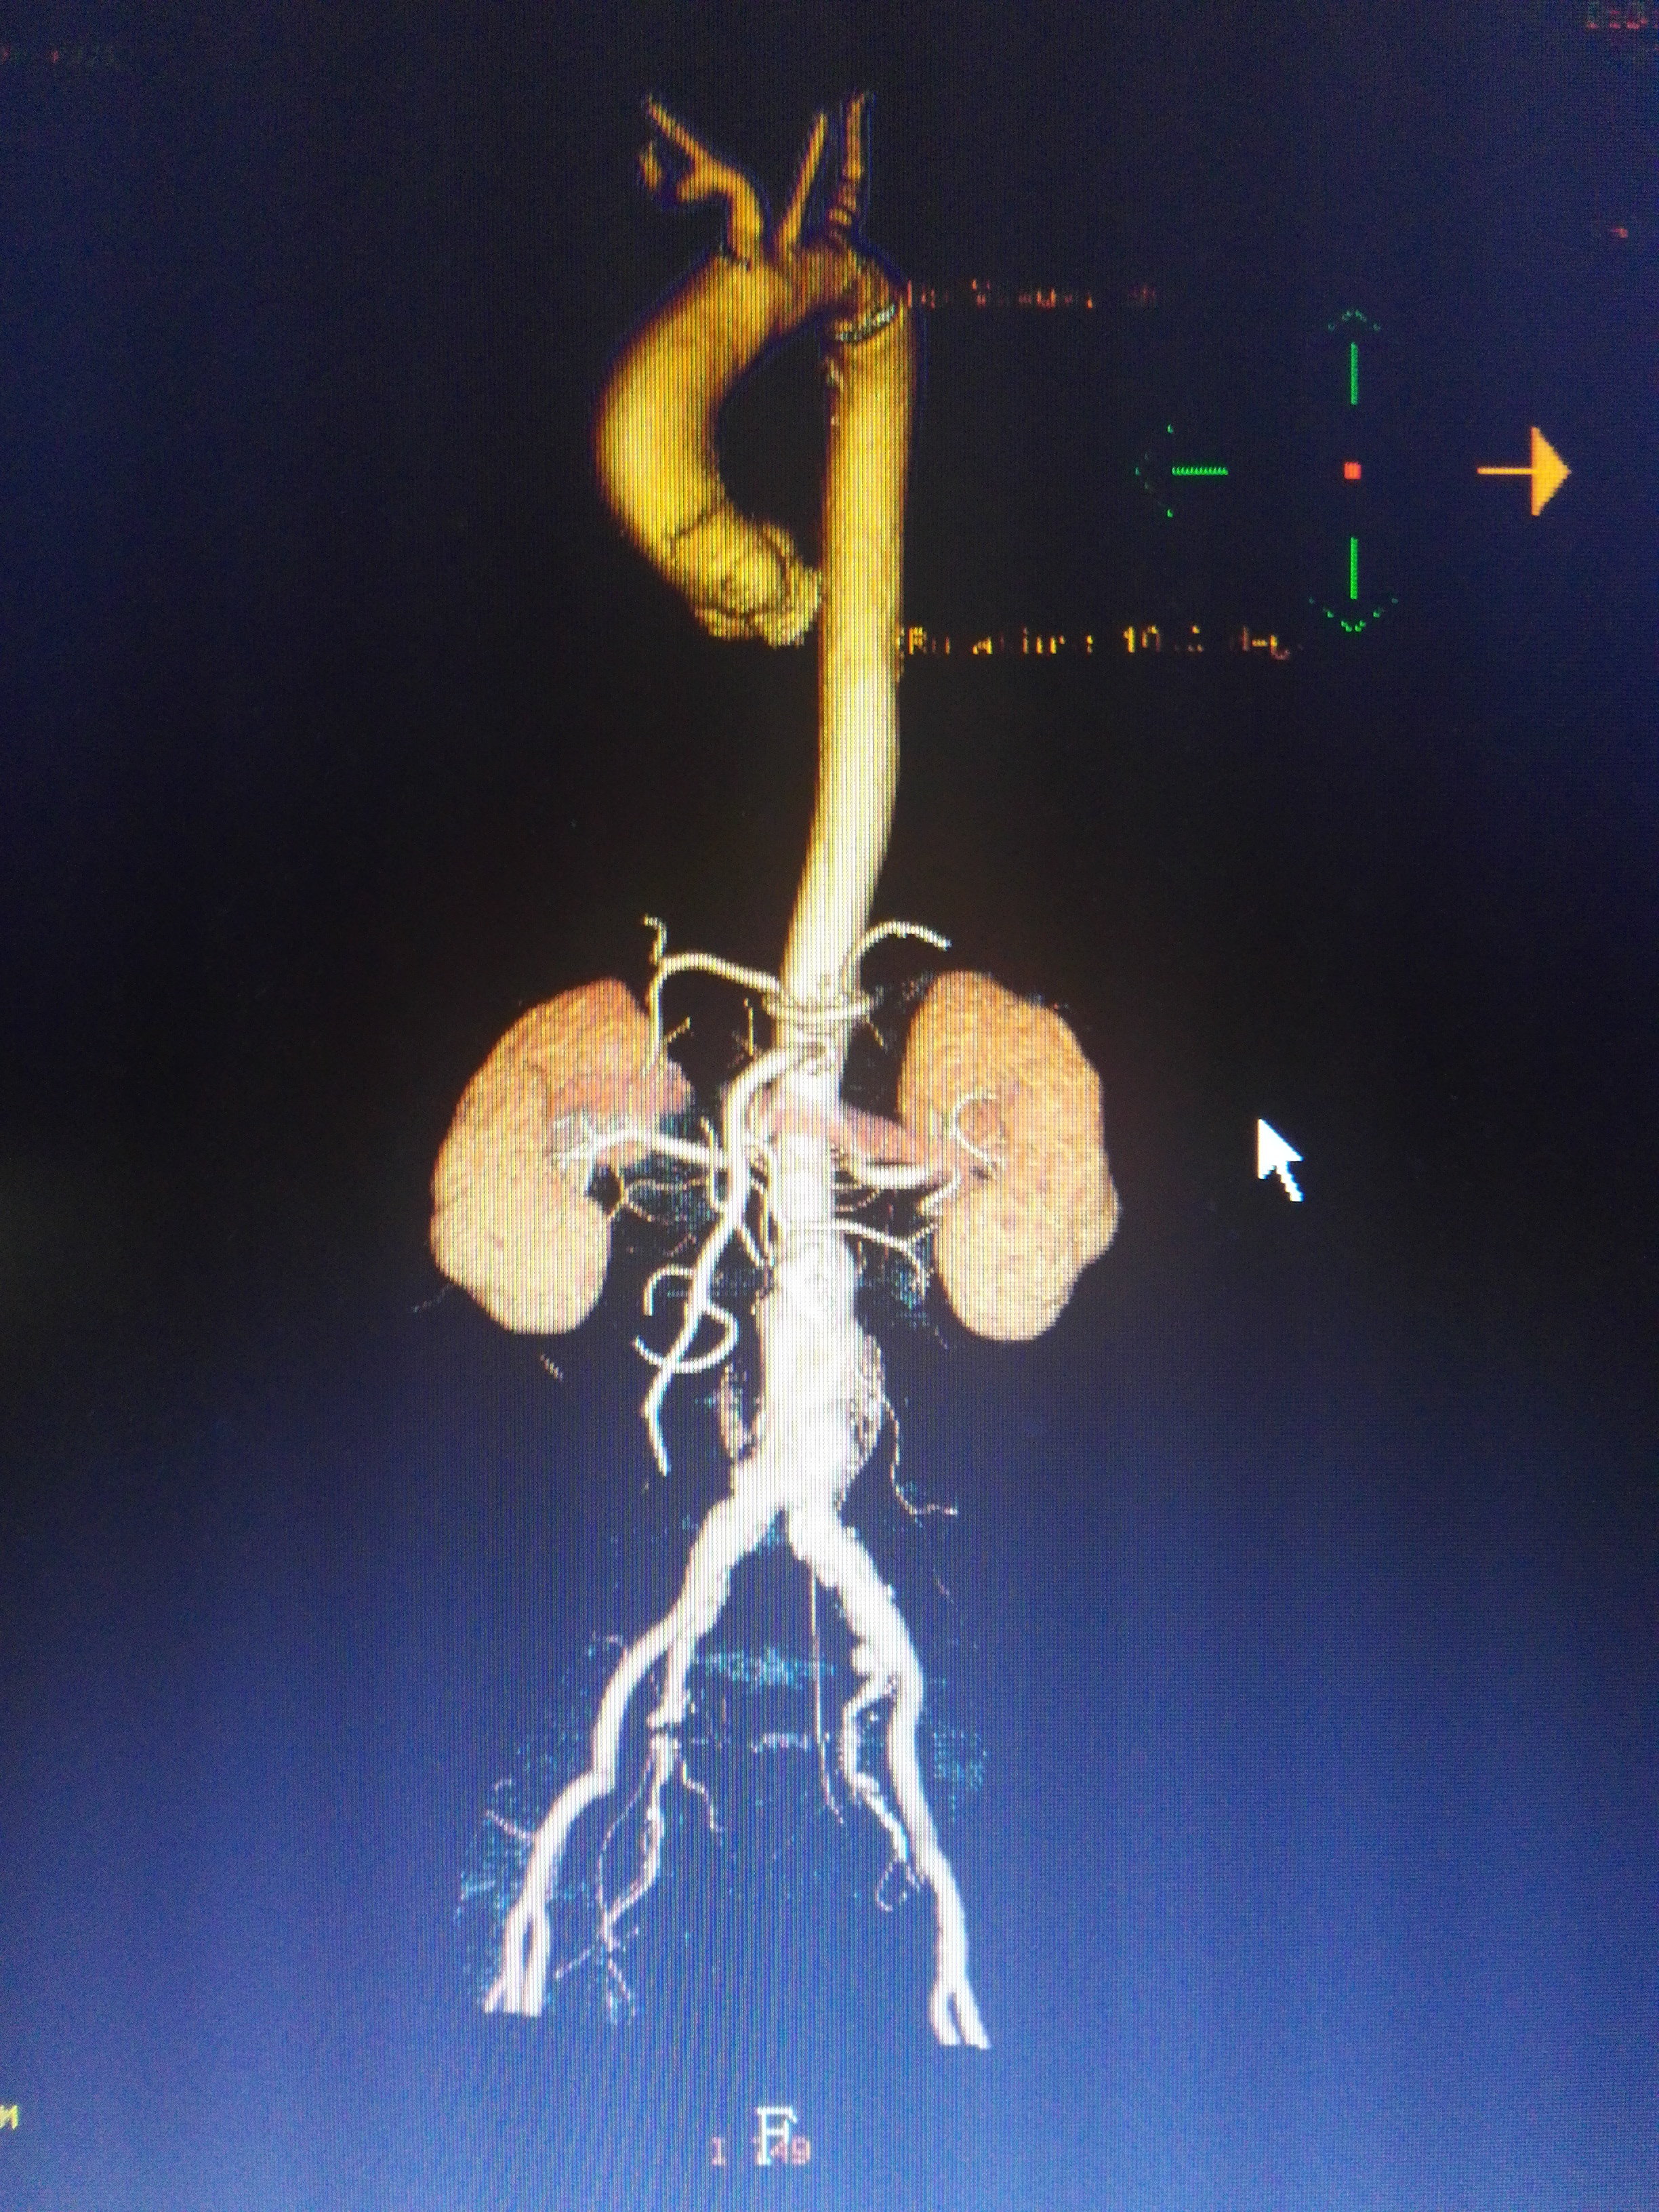

其它 腹主动脉瘤 写美篇ct 术中标记导管显示长度 术后造影

其它 腹主动脉瘤 写美篇患者ct 术后造影

腹主动脉瘤腔内修补及术后随访影像评估

近期腹主动脉瘤腔内隔绝术一例